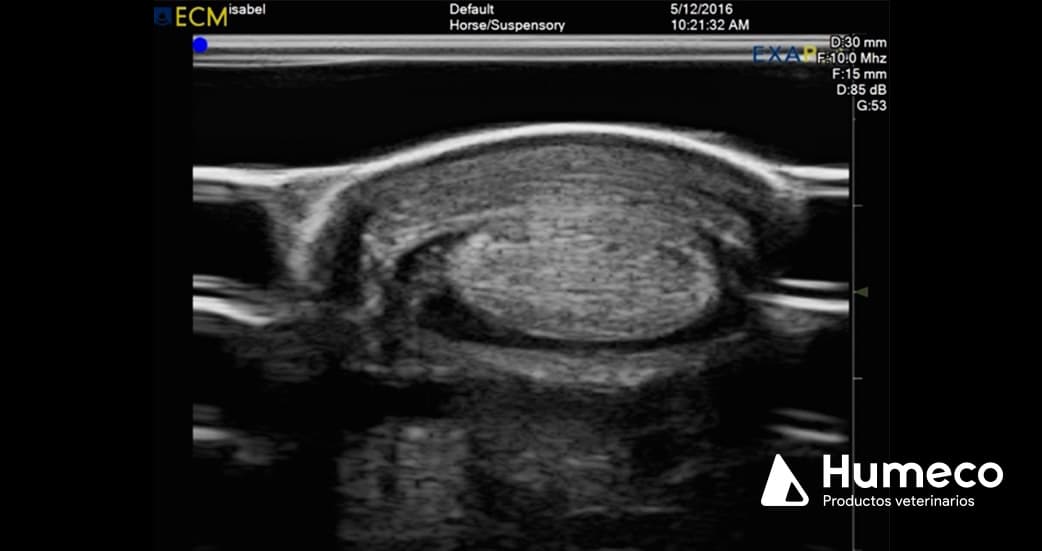

Lo primero es llegar a un diagnóstico certero, en el que se requiere una ecografía de la zona (tendón, ligamento…). Una vez diagnosticado, se lleva a cabo la aplicación de la corriente, que para que sea eficaz, debe ser muy precisa y ecoguiada.

Por ello, una grandísima parte del buen resultado de la Técnica, es la ecografía músculo-esquelética.

Con EXAPAD disponemos de un equipo idóneo con una calidad de imagen del más alto nivel para la realización de diagnóstico y tratamiento de lesiones músculo-esqueléticas.